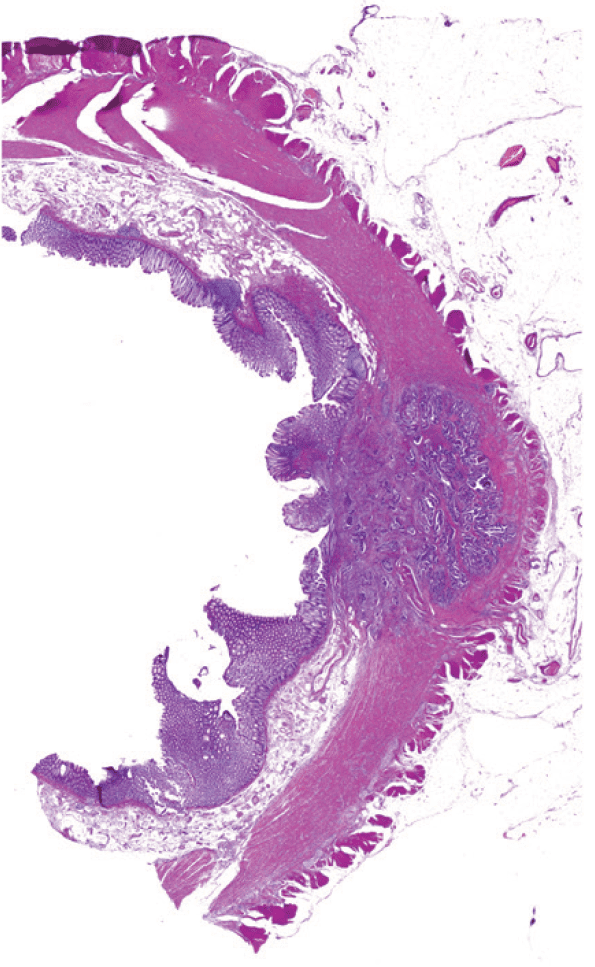

Representative images of H&E stained colorectal tumour showing spatial enrichment using Laser Microdissection (LMD).

(1) Prior to dissection

(2) Areas of interest annotated

(3) Tissues dissected

Figure 1: (1) Patient sample prior to dissection under the LMD. (2) Patient sample with tumour regions (red) and adjacent normal tissues (green) annotated to be microdissected. (3) Patient sample after all tissues of interest were dissected and collected into a 0.6 mL tube cap, with muscular/ adipose tissues remaining in the section. Magnification 2.5x.

Laser microdissected samples were captured with cut areas of approximately 100 × 106 μm2 for ~ 20μg of protein from colorectal cancer and normal adjacent samples (Figure 1). Digested samples were purified using StageTips, then reconstituted in 0.1% FA.